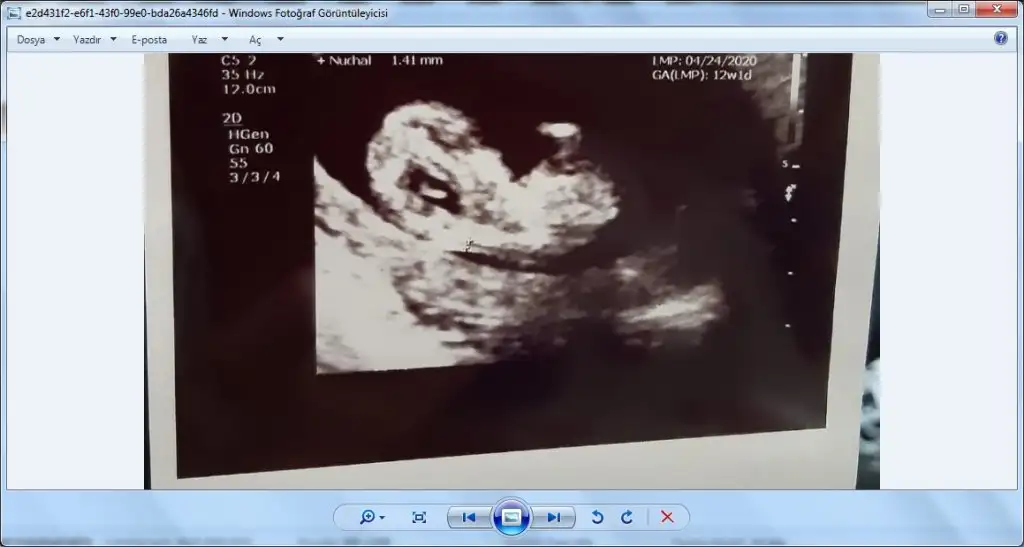

Ama nub için 11 12 13 haftalar olmalı sanırım bu 14-15 hafta gibi

Kızlar tahminleri alalım nub prosu var dediler geldik.